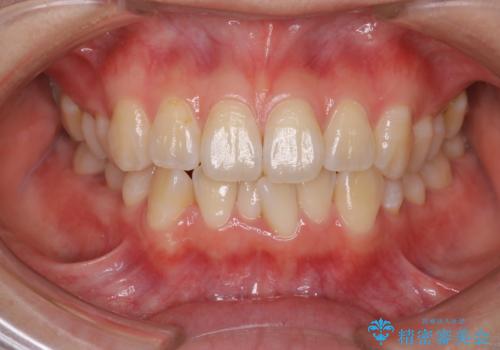

前歯のガタガタを治したい。

- 凸凹を治したいと来院された患者様です。

インビザラインにて、遠心移動を行いながら綺麗に配列することができました。